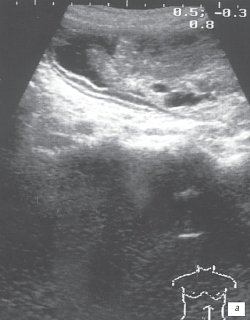

Учитывая молодой возраст пациентки, значительные размеры опухоли в желудке, документированные рентгеновскими снимками, было решено выполнить контрольное ультразвуковое исследование органов брюшной полости. В печени, желчном пузыре, поджелудочной железе (рис. 2), селезенке и забрюшинном пространстве эхоструктурных изменений не выявлено.

Рис. 2. Эхограмма поджелудочной железы.